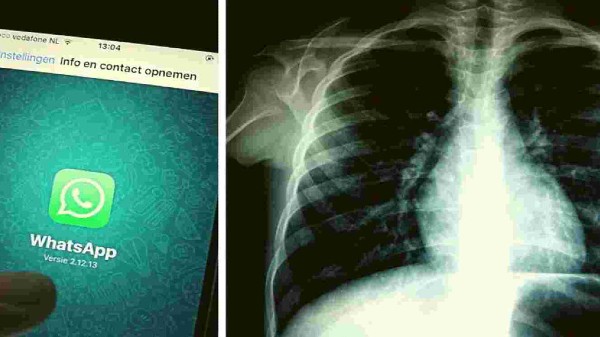

ಪ್ರಸ್ತುತ ದಿನಗಳಲ್ಲಿ ಕೊರೊನಾ ಎರಡನೇ ಅಲೆ ವ್ಯಾಪಕವಾಗಿ ಹರಡುತ್ತಿದೆ. ಇದನ್ನು ನಿಯಂತ್ರಣಕ್ಕೆ ತರುವ ನಿಟ್ಟಿನಲ್ಲಿ ಸರ್ಕಾರ ಕೂಡ ಕಾರ್ಯನಿರ್ವಹಿಸುತ್ತಿದೆ. ಈಗಾಗಲೇ ಕೊರೊನಾ ಅಲೆ ನಿಯಂತ್ರಣಕ್ಕೆ ಹಲವಾರು ಕ್ರಮ ಕೈ ಗೊಂಡಿರುವ ಸರ್ಕಾರ ಇದೀಗ ಹೊಸ ಅಪ್ಲಿಕೇಶನ್ ಒಂದನ್ನು ಪರಿಚಯಿಸಿದೆ. ಸದ್ಯ ಇದೀಗ ಸರ್ಕಾರವು ಕೃತಕ ಬುದ್ಧಿಮತ್ತೆ ಆಧಾರಿತ ಎಕ್ಸ್-ರೇ ಸೇತುವನ್ನು ಪ್ರಾರಂಭಿಸಿದೆ, ಇದನ್ನು ವಾಟ್ಸಾಪ್ ಮೂಲಕ ಕೂಡ ನಿರ್ವಹಿಸಬಹುದಾಗಿದೆ.

ಹೌದು, ಸರ್ಕಾರ ಎಕ್ಸ್ರೇ ಸೇತು ಎನ್ನುವ ಅಪ್ಲಿಕೇಶನ್ ಪರಿಚಯಿಸಿದೆ. ಇದು ಕೃತಕ ಬುದ್ದಿಮತ್ತೆ ಆಧಾರದಲ್ಲಿ ಕಾರ್ಯನಿರ್ವಹಿಸಲಿದೆ. ನಿಮ್ಮ ಎದೆಯ ಎಕ್ಸ್ರೇ ಬಳಸಿ ಕೋವಿಡ್ ಅನ್ನು ಕಂಡುಹಿಡಿಯುವ ಕಾರ್ಯವನ್ನು ಈ ಅಪ್ಲಿಕೇಶನ್ ಮಾಡಲಿದೆ. ಇದನ್ನು ವಾಟ್ಸಾಪ್ ಮೂಲಕ ಬಳಸಬಹುದಾಗಿದೆ. ಕೋವಿಡ್ ಪತ್ತೆಗಾಗಿ ಮೂಲ ಡಿವೈಸ್ಗಳಿಗೆ ಹೆಣಗಾಡುತ್ತಿರುವ ಗ್ರಾಮೀಣ ವೈದ್ಯರಿಗೆ ಇದು ಪ್ರಮುಖ ಸಾಧನವಾಗಲಿದೆ. ಇದಕ್ಕಾಗಿ ಸರ್ಕಾರವು ಲಾಭೋದ್ದೇಶವಿಲ್ಲದ ಸಂಸ್ಥೆ ಆರ್ಟ್ಪಾರ್ಕ್ ಮತ್ತು ನಿರಮೈ ಅವರೊಂದಿಗೆ ಪಾಲುದಾರಿಕೆ ಹೊಂದಿದೆ. ಹಾಗಾದ್ರೆ ಈ ಅಪ್ಲಿಕೇಶನ್ ವಿಶೇಷತೆ ಏನು ಅನ್ನೊದನ್ನ ಈ ಲೇಖನದಲ್ಲಿ ತಿಳಿಸಿಕೊಡ್ತಿವಿ ಓದಿರಿ.

ಬೆಂಗಳೂರು ಮೂಲದ ಸ್ಮಾರ್ಟ್ಅಪ್ ಸಂಸ್ಥೆಯೊಂದು ಈ ಅಪ್ಲಿಕೇಶನ್ ಅನ್ನು ರೂಪಿಸಿದೆ. ಈ ಅಪ್ಲಿಕೇಶನ್ ಬಳಸಿ ಕೋವಿಡ್ ಟೆಸ್ಟ್ ಅನ್ನು ಮಾಡಬಹುದಾಗಿದೆ. ಇದರಲ್ಲಿರುವ ಎಐ ತಂತ್ರಜ್ಞಾನದ ಮೂಲಕ ಇದು ಸಾಧ್ಯವಾಗಲಿದೆ. ಅಂದರೆ ವಾಟ್ಸಾಪ್ ಮೂಲಕ ಕಳುಹಿಸಿದ ಎಕ್ಸ್ರೇ ಚಿತ್ರಗಳನ್ನು ಪರಿಶೀಲಿಸಿ ಕೋವಿಡ್ ವರದಿಯನ್ನು ನೀಡುವ ಸಾಮರ್ಥ್ಯವನ್ನು ಈ ಅಪ್ಲಿಕೇಶನ್ ಹೊಂದಿದೆ. ಎಐ ಸಿಸ್ಟಮ್ನೊಂದಿಗೆ ಸಂಸ್ಕರಿಸಿದ ಎಕ್ಸರೆ ಬಳಸಿ COVID-19 ಅನ್ನು ಕಂಡುಹಿಡಿಯಲು ಹೊಸ ತಂತ್ರಜ್ಞಾನವು ಸಹಾಯ ಮಾಡುತ್ತದೆ. ಇದಕ್ಕಾಗಿ ಪ್ರಸ್ತುತ ಯಾವುದೇ ಶುಲ್ಕ ವಿಧಿಸಲಾಗುವುದಿಲ್ಲ ಎನ್ನಲಾಗಿದೆ.